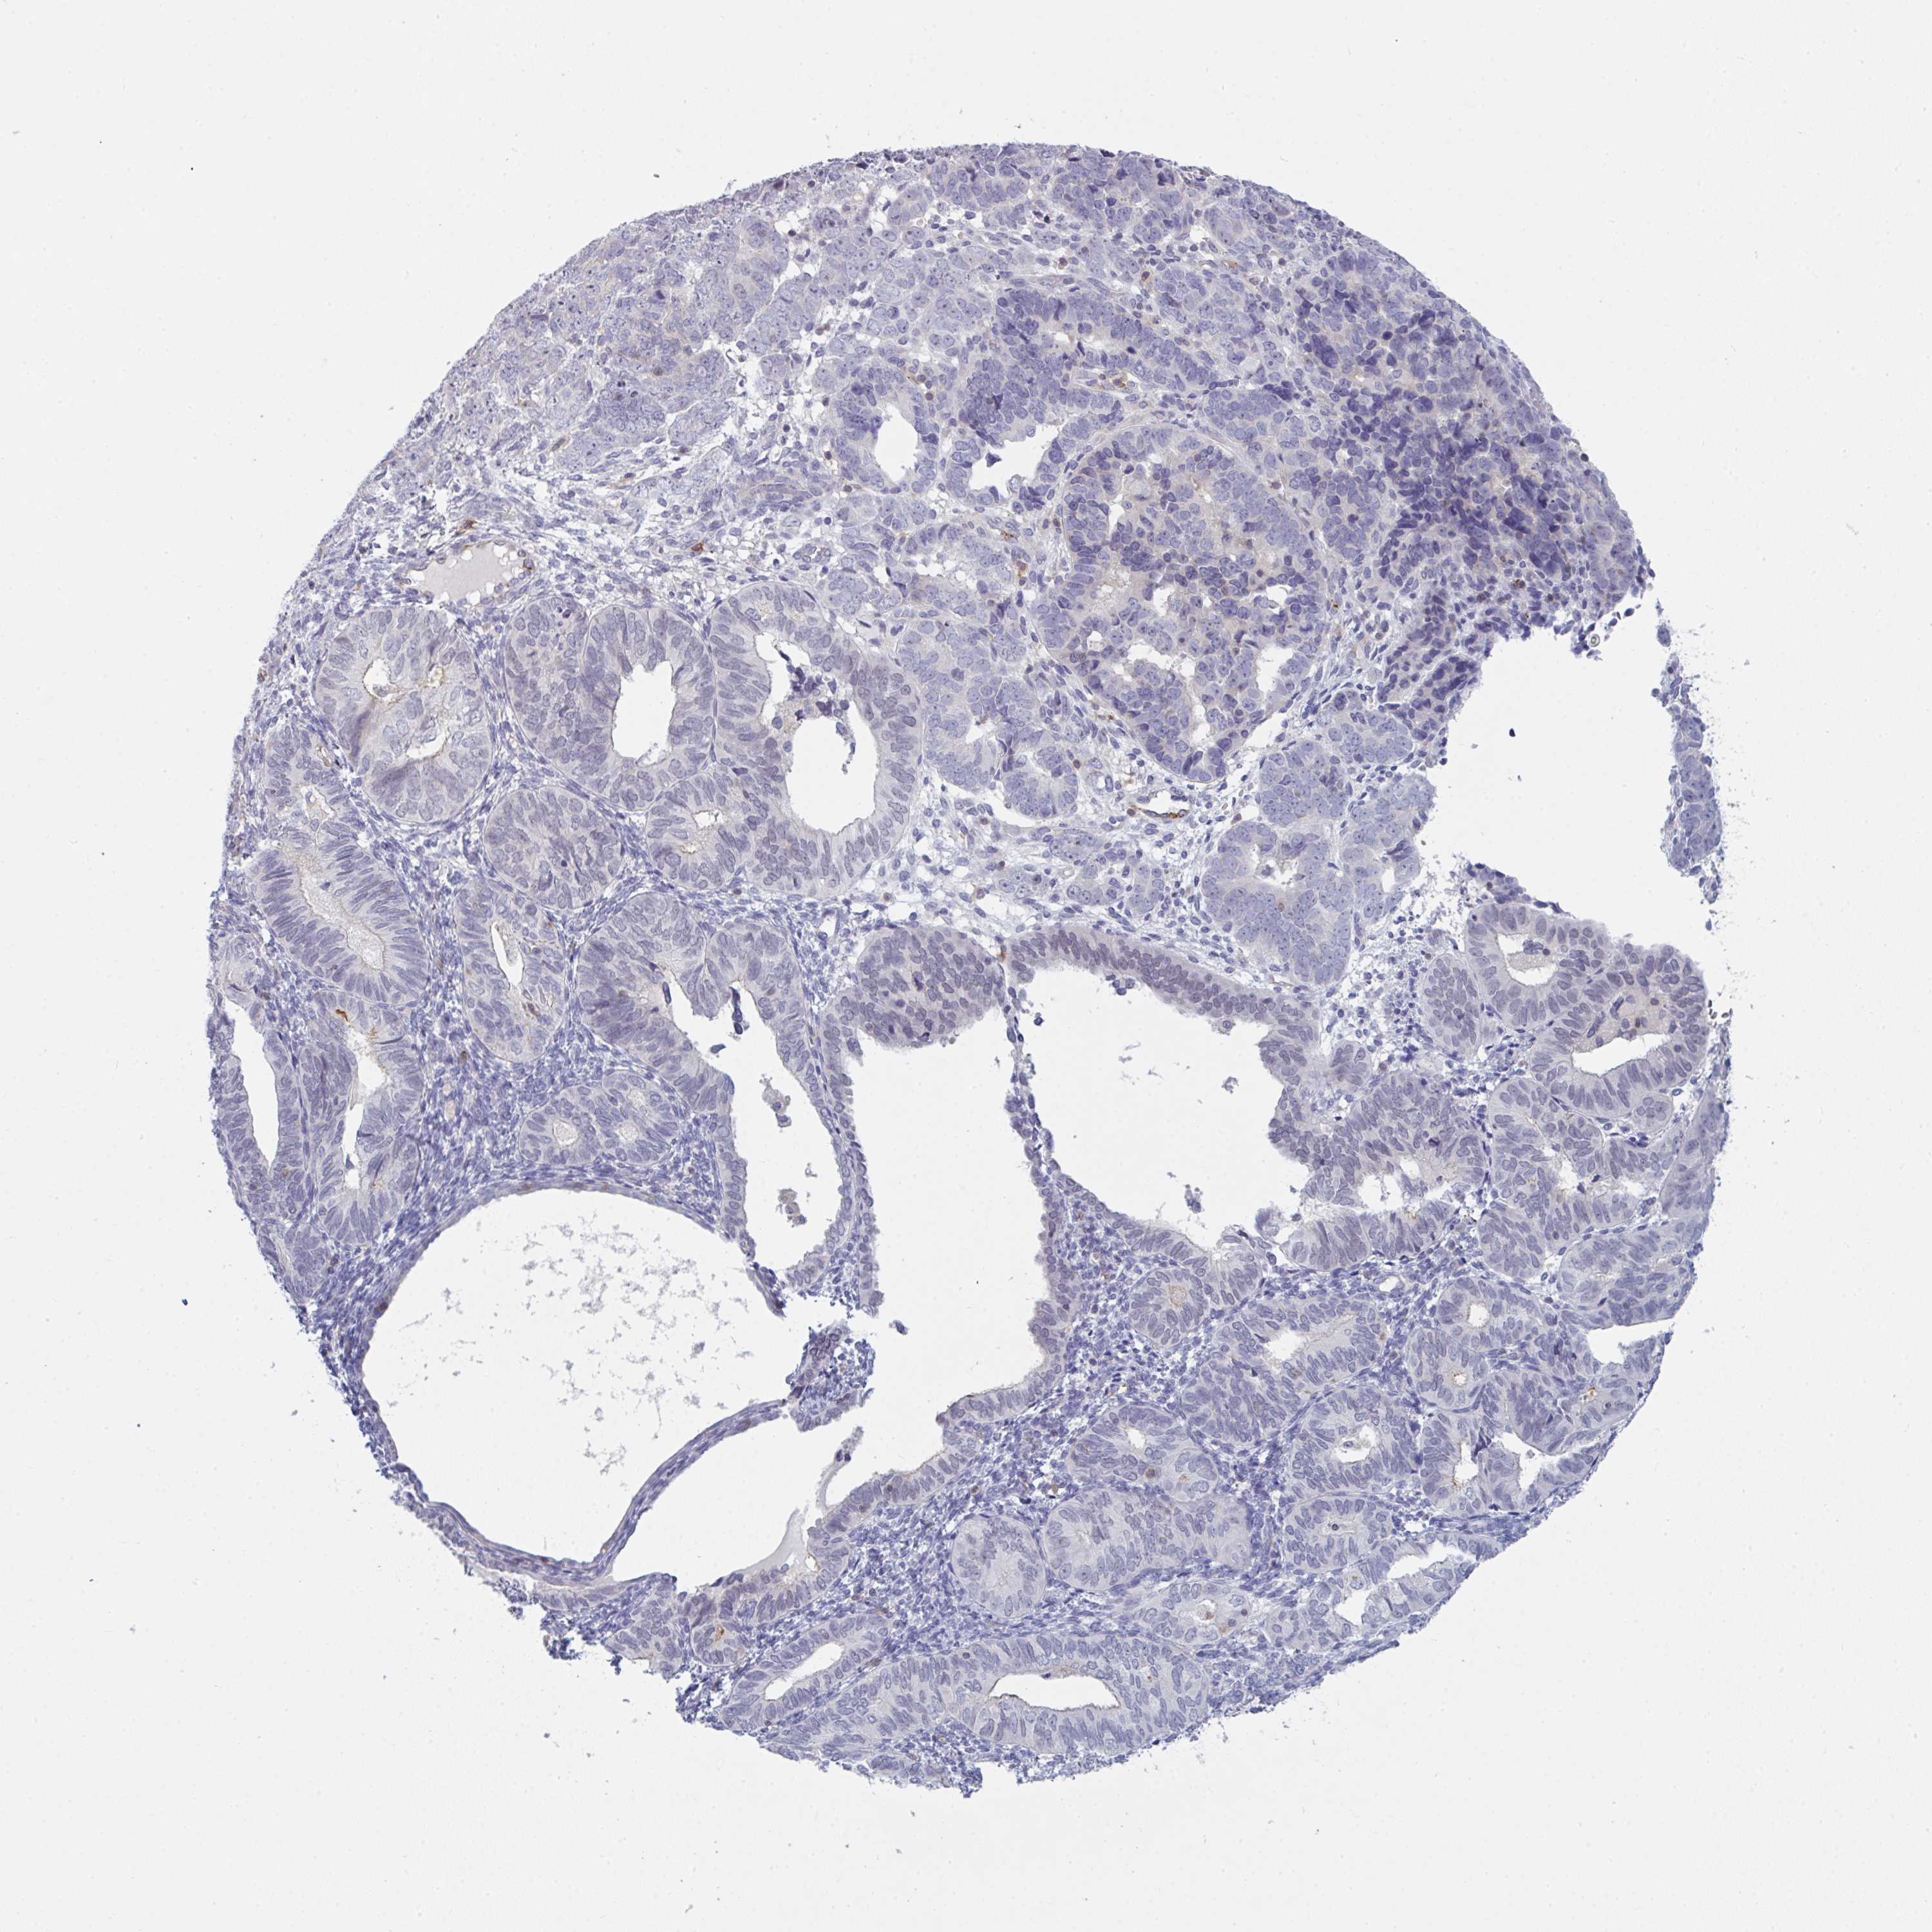

ENDOMETRIAL CANCER - Protein expressioni

A mouse-over function shows sample information and annotation data. Click on an image to view it in a full screen mode. Samples can be filtered based on level of antibody staining by selecting one or several of the following categories: high, medium, low and not detected. The assay and annotation is described here.

Note that samples used for immunohistochemistry by the Human Protein Atlas do not correspond to samples in the TCGA dataset.

Antibody stainingi

Antibody staining in the annotated cell types in the current human tissue is reported as not detected, low, medium, or high, based on conventional immunohistochemistry profiling in selected tissues. This score is based on the combination of the staining intensity and fraction of stained cells.

Each image is clickable and will lead to virtual microscopy that enables deeper exploration of all samples and also displays staining intensity scores, fraction scores and subcellular localization as well as patient and tissue information for each sample.

Antibody HPA050092

Antibody CAB025368

Staining

High

Medium

Low

Not detected

Intensity

Strong

Moderate

Weak

Negative

Quantity

>75%

75%-25%

<25%

None

Location

Nuclear

Cytoplasmic/membranous

Cytoplasmic/membranous,nuclear

Adenocarcinoma, NOS

Carcinoma, NOS

Adenocarcinoma, metastatic, NOS